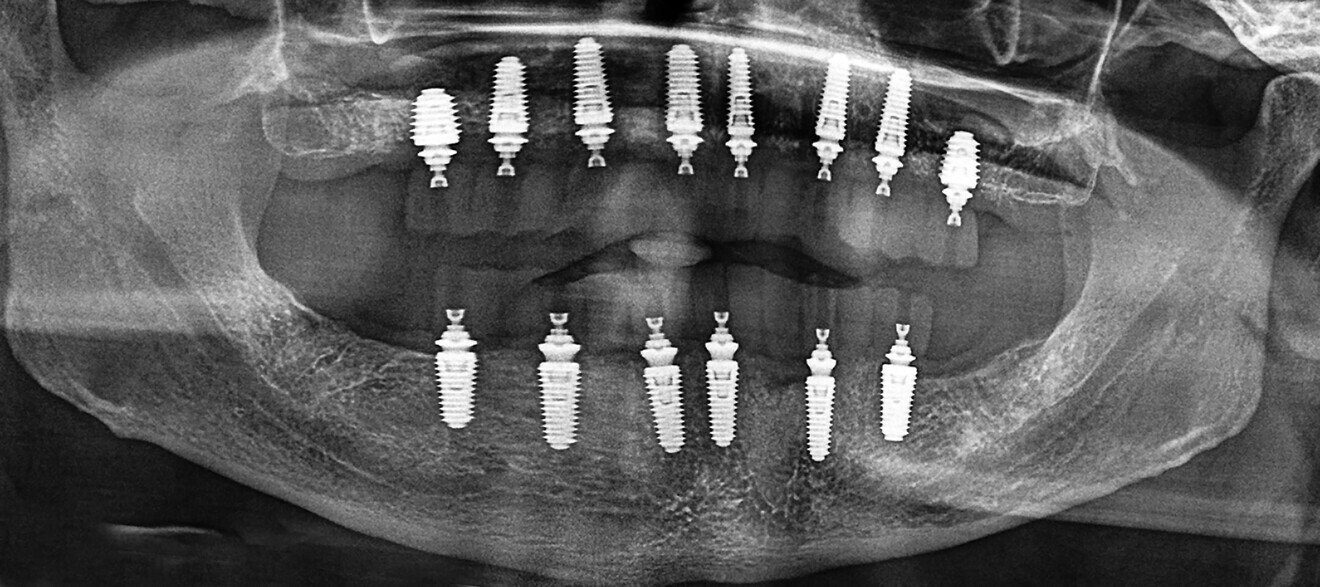

Fig. 16a: Panoramic radiograph showing printed restorations secured with Grammetry Vortex LA VIS screws.

Fig. 17a: Final panoramic radiograph confirming seating of the zirconia restorations.

The data collected was sent through a scanning software portal (Medit Scan for Clinics) to the dental laboratory with requested changes for correction of the desired smile design. Utilising advanced planning features in the design software (exocad), the midline and tooth size changes were corrected. 3D-printed maxillary and mandibular PMMA restorations were used for try-in using the direct-to-MUA screws (Vortex LA VIS; Fig. 16a). Fit, phonetics, aesthetics and occlusion were evaluated and confirmed using digital articulation (OccluSense; Fig. 16b). The patient was extremely satisfied with the printed try-ins. Since no adjustments were required, the patient was allowed to leave with the printed try-ins as new provisional restorations made from extra-strong resin. The new provisional restorations were worn for ten days to confirm form and function. The final shade was chosen, and metal-free monolithic zirconia restorations were then fabricated by the laboratory.

The final restorations were passively and accurately seated ten days later uneventfully using Vortex LA VIS screws. Confirmation records were taken with photographs, radiographs and digital articulation to recheck fit, function, phonetics and occlusion (Fig. 17a). The patient was extremely satisfied with his final restorations, describing the process as life-changing and surprisingly fast in comparison with what he had heard about full-mouth implant therapy. He was especially pleased with the speed at which the final process was able to be completed (Figs. 17b & c).